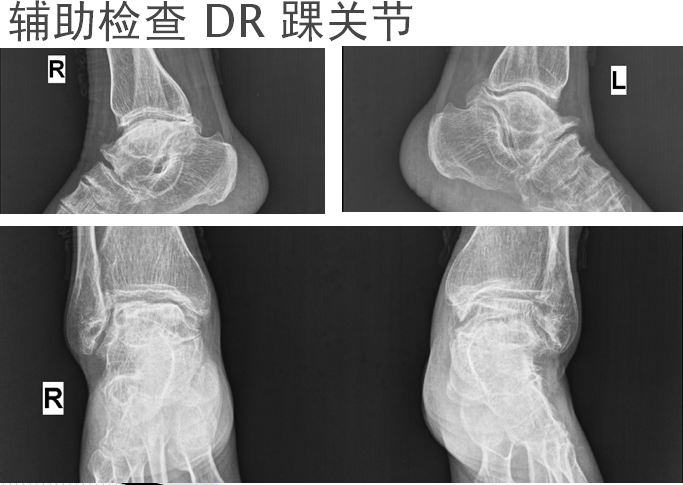

患者:何某某,女,52岁。出生成长于大骨节病流行病区

主诉:反复四肢多关节疼痛伴活内受限30﹢年

现病史:自述30﹢年前无诱因出现双踝、双膝、双髋、双腕关节隐痛,受凉、晨起疼痛明显。并感四肢僵硬感,保暖、适当活动可减轻。于当地医院就诊,诊断为“骨性关节炎”,予药物(具体不详)治疗,疼痛可暂时减轻,但停药后疼痛反复,并逐渐伴上述关节活动受限。患者间断于外行理疗对症,症无完全缓解。不伴游走性关节红肿热,不伴低热、盗汗、进行性消瘦、夜间痛甚等。为进一步治疗,遂于今日入我院。

1.大骨节病

2.双踝、双膝、双髋骨性关节炎